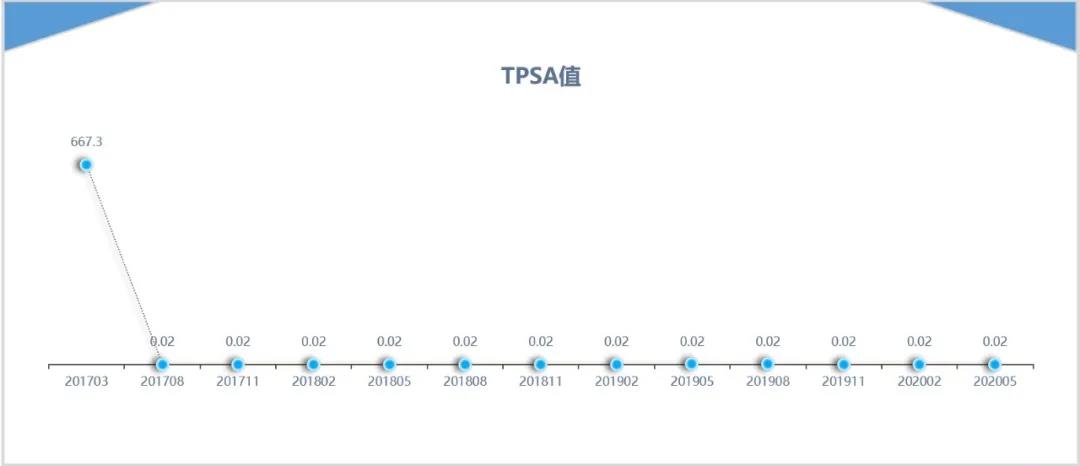

病史介绍 患者张某某,男性,80岁; 2017年3月因腰部疼痛,下肢不适,麻木感,于2017年3月在当地医院检查前列腺特异性抗原(PSA)&g...